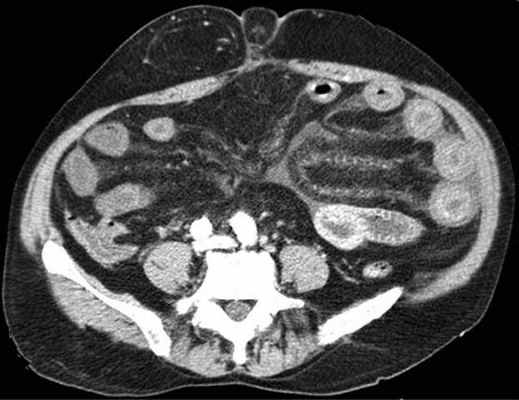

На рентгенограммах, полученных в положении стоя или лежа на боку, обычно видны горизонтальные уровни жидкости и газа (рис. 2). Рисунок 2. Обзорная рентгенограмма брюшной полости. Видны чаши Клойбера, уровни жидкости. Заполненные газом кишечные петли имеют вид опрокинутых чаш (чаши Клойбера). Они появляются при странгуляции через 1-2 ч после начала заболевания, при обтурации - через 3-5 ч. По размерам чаш Клойбера, их форме и локализации можно судить об уровне непроходимости.

При тонкокишечной непроходимости чаши Клойбера небольших размеров, ширина горизонтального уровня жидкости больше, чем высота столба газа над ним. Обычно наблюдается большое количество горизонтальных уровней с изменением их расположения в течение времени и перемещением жидкости из одной петли в другую. Горизонтальные уровни жидкости ровные. На фоне газа хорошо видны складки слизистой оболочки (складки Керкринга), принимающие форму растянутой спирали.

При непроходимости тощей кишки горизонтальные уровни жидкости локализуются в левом подреберье и эпигастральной области. При непроходимости в терминальном отделе подвздошной кишки уровни жидкости расположены в области мезогастрия.

При тонкокишечной непроходимости, кроме чаш Клойбера, на рентгенограммах видны растянутые газом кишечные петли, принимающие форму «аркад» или «органных труб», похожих на перевернутые буквы J и U.

При толстокишечной непроходимости горизонтальные уровни жидкости расположены по периферии брюшной полости, в боковых отделах живота, и их меньше, чем при тонкокишечной непроходимости. Высота чаш Клойбера преобладает над шириной. На фоне газа видны полулунные складки слизистой оболочки («гаустры»). Уровни жидкости не имеют ровной поверхности («зеркала»), что обусловлено наличием в толстой кишке плотных кусочков кала, плавающих на поверхности жидкого кишечного содержимого.